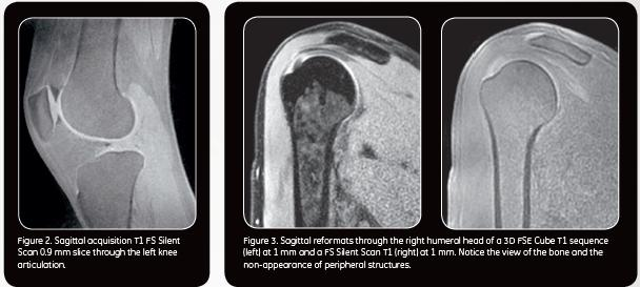

Los médicos del hospital madrileño, que está reconocido por la FIFA como centro médico de excelencia, serán de los primeros de Europa en utilizar una innovadora tecnología de RM de 1,5T denominada Signa Voyager*, una de cuyas principales características es su capacidad para poder suministrar imágenes de alta calidad del hueso cortical, es decir de la capa exterior del hueso, algo que, hasta ahora solo estaba al alcance del TAC o de la radiografía convencional.

Tal como destaca el Dr. Mario Padrón, jefe del Servicio de Radiodiagnóstico de la Clínica CEMTRO, "la gran ventaja de esta nueva tecnología que estamos validando en la clínica es que permitirá poder ver y diferenciar claramente en una sola prueba las partes duras y la estructura periférica de los huesos, es decir, las partes blandas que lo rodean como músculos, tendones, grasa y tejidos fibrosos". Según el Dr. Padrón, "esto puede que evite en muchos casos, tener que exponer al paciente a una segunda prueba como el TAC, que es preferible no realizar si no es estrictamente necesario, sobre todo en niños y en pacientes que han de someterse a muchas pruebas".